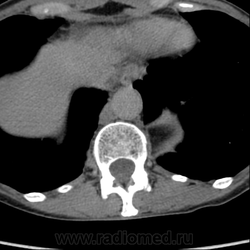

Обнаружилось небольшое образование низкой плотности, с достаточно ровными, четкими контурами парааортально справа около ножки диафрагмы на уровне тела L1 позвонка.

При нативе плотность 6HU, паренхиматозная - 18-20HU, экскреторная (15 минут) - 60-65HU.

Выкладываю по очереди срезы на одинаковых уровнях, сначала паренхиматозная, потом отсроченная фазы.

Цистерна грудного лимфатического протока? Я в кт ноль :)